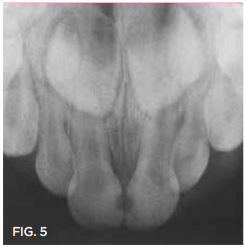

Case 3. This 10-year-old boy was brought to the office for a second opinion regarding restoration of the left primary first molar, which was causing sensitivity (Figure 8). The boy's mother reported that a "tooth-colored filling" had been suggested at another office. The boy was terrified of needle injections and, according to his mother, had required sedation in prior years for restoration of maxillary primary molars. SDF was applied (Figure 9), tooth sensitivity was eliminated, and in 3 months, clinical evaluation and a periapical radiograph confirmed that no other treatment would be needed until the tooth exfoliated (Figure 10 and Figure 11).

Fig 8. 10-year-old patient with distal caries lesion of primary  rst molar. (

Fig 8

Fig 11. 3 months after SDF application, no additional treatment needed.

Fig 11